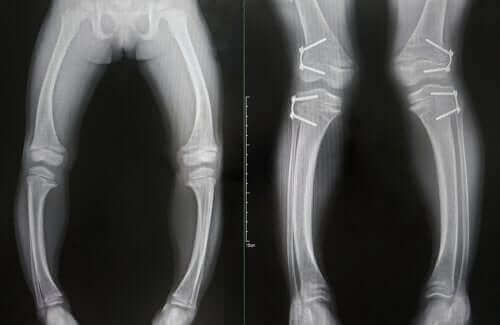

- Kemiklerde yumuşama gibi bozukluklar. Bu tarz bozukluklar genellikle raşitizm hastalarının eğri kemiklere sahip olmasına neden olur. Ayrıca, bazı kemik uçlarında yıpranmalar da görülebilir.

Tahliller ve çekilen röntgenlere dayalı bazı bulgular ve yukarıda bahsettiğimiz diğer klinik belirtilerin gözlemlenmesi bu hastalığın teşhis edilmesinde yardımcı olan öğelerdendir.